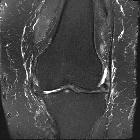

MRI

MRI is the modality of choice for assessing patellar cartilage.

- T2/PD

- best sequences for assessing cartilage

- most patients with chondromalacia patellae have focally increased signal in the cartilage or focal contour defects in the cartilage surface

- abnormal cartilage is usually of high signal compared to normal cartilage

- findings range from a subtle increase in signal to complete loss of cartilage

- the grading system of chondromalacia patellae is based on T2/PD weighted MRI findings and arthroscopic correlation: see chondromalacia grading (Outerbridge method) or modified Noyes